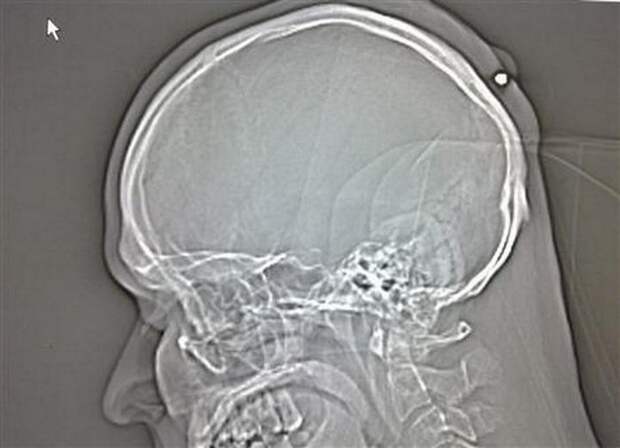

Свинцовое похмелье

35-летнему поляку выстрелили в голову, когда тот был пьян, он даже не заметил этого. В итоге пуля была случайно обнаружена пять лет спустя.